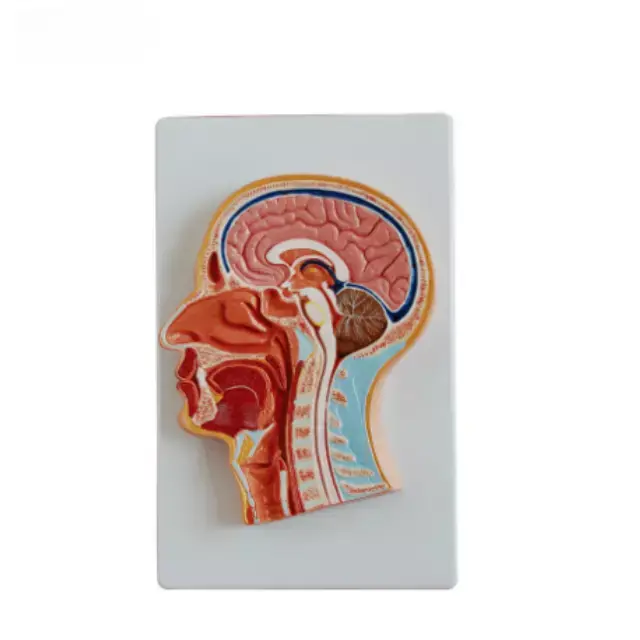

Sección Frontal Media de la Cabeza Serie

Descripcion general